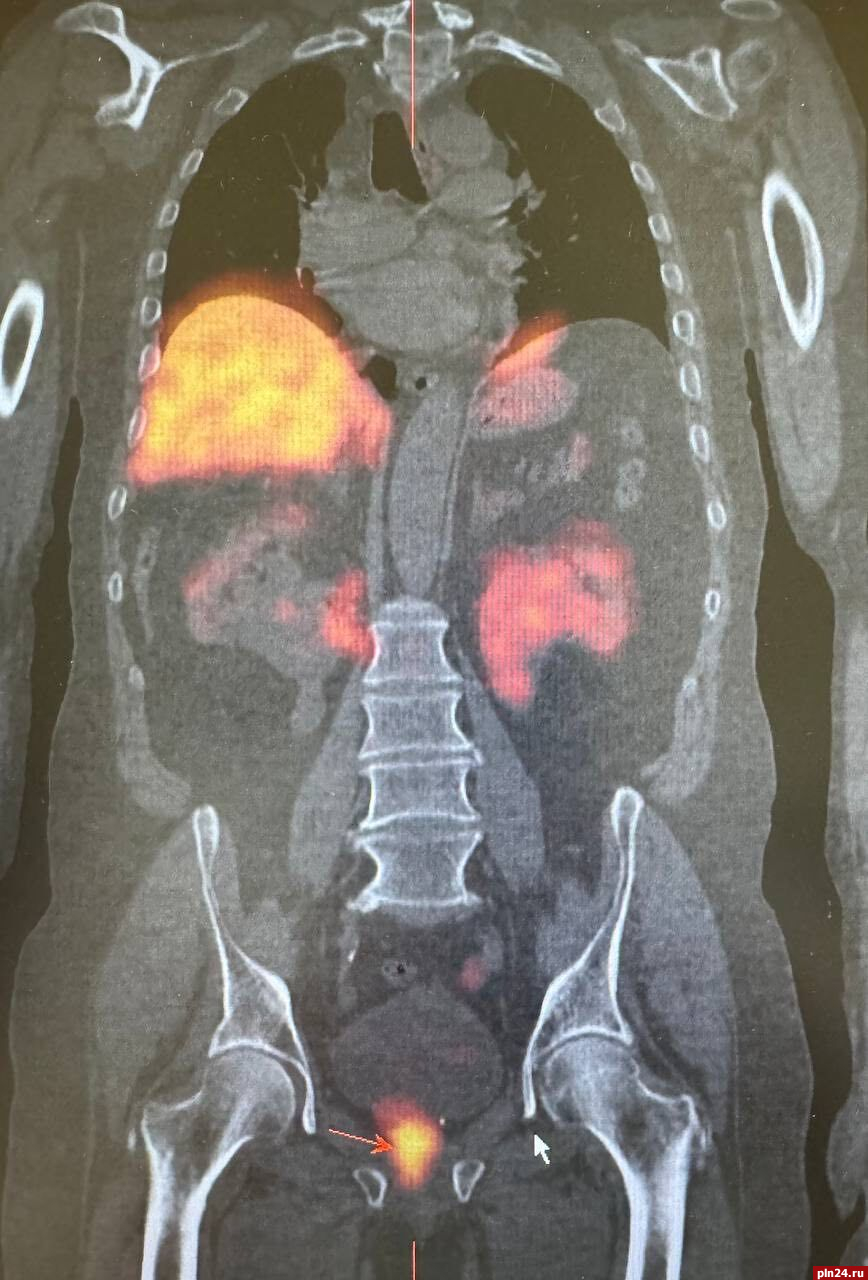

Для уточнения диагноза и получения более детальной информации о состоянии лимфатических узлов была назначена радионуклидная диагностика. Этот метод позволил более точно определить наличие злокачественного опухолевого процесса в предстательной железе, а также подтвердить метастатическое поражение ранее выявленных лимфатических узлов в грудной клетке. Кроме того, радионуклидное исследование показало активное накопление технеция ПСМА в парааортальных лимфатических узлах с обеих сторон.

При этом важно отметить, что на компьютерной томографии не было явных структурных изменений, что затрудняло оценку их состояния и возможности метастазирования, уточнили в министерстве.

Таким образом, результаты радионуклидной диагностики стали решающими в выявлении вторичного поражения лимфатических узлов. Это позволило врачам незамедлительно начать специализированное лечение, что значительно повысило шансы пациента на успешное преодоление заболевания.